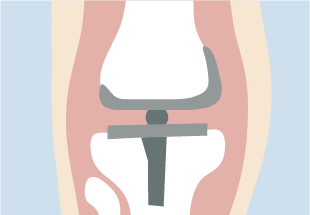

- 進行期〜末期

- 痛みや歩行障害が悪化した場合の選択肢は、手術です。高位脛骨骨切り術、人工関節置換術などがあります。